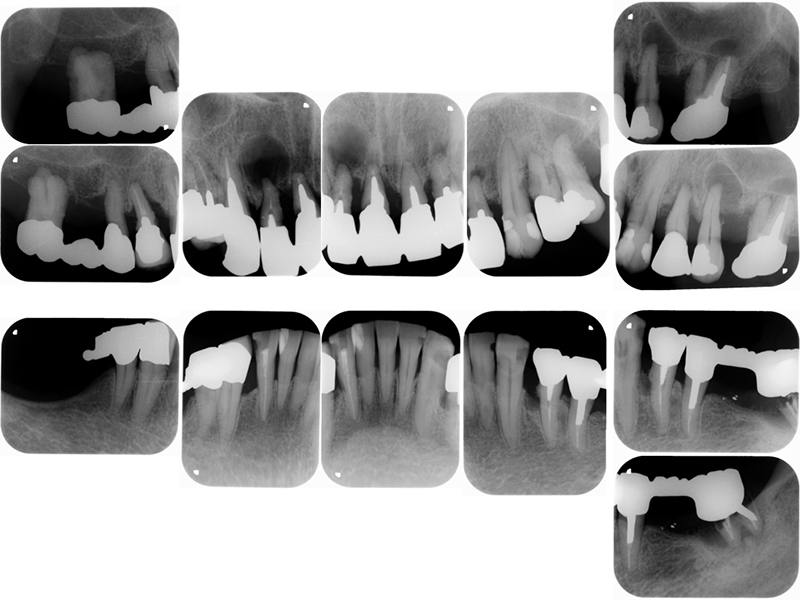

治療前X線写真